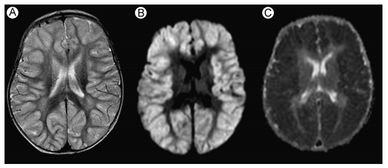

神经系统是人体内负责传递信息、调节生理和心理活动的系统。它主要由大脑、脊髓和神经组成。大脑负责处理复杂的信息,脊髓负责传递信息,神经则负责将信息传递到身体的各个部位。